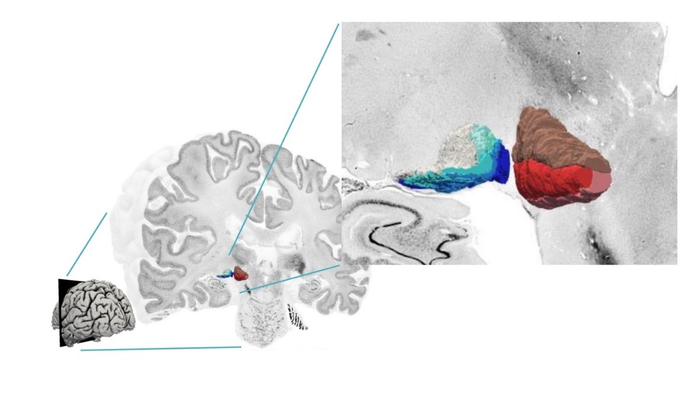

The human metathalamus is extremely important for relaying auditory and visual signals to the rest of the brain. However, a detailed, three-dimensional map of the cellular structure of the area was still missing. Using the BigBrain dataset, an integral part of the HBP, the researchers focused on the two distinct parts of the metathalamus: the medial geniculate body (MGB) with its subdivisions; and lateral geniculate body (LGB) with its six layers.

“The BigBrain dataset helps us to understand the structure of complex subcortical nuclei” explains Andrea Brandstetter of the Institute of Neuroscience and Medicine, Forschungszentrum Jülich, in a video by HBP partnering project HIBALL . "Novel deep-learning-based approaches are used to learn about the topography and the cellular architecture of the metathalamus” continues Kai Kiwitz of the Cécile and Oskar Vogt Institute of Brain Research, University Hospital Düsseldorf.

The new 3D maps are freely available online as part of the EBRAINS Atlas; you can navigate them here . “This way they can be used by the scientific community to bridge the microscale histology of BigBrain with functional measurements” explains Kiwitz. In addition to expanding our knowledge of the brain structure, the maps also have clinical relevance: many neurological disorders and dysfunctions involve the metathalamus, and highly detailed information regarding these structures could be used in conjunction with neuroimaging to better inform diagnosis and aid neurosurgery and deep brain stimulation.